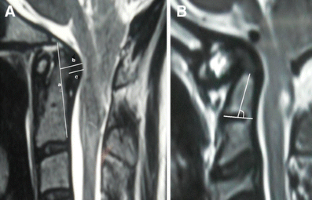

Sixteen adult patients with Chiari I malformation with significant ventral cervicomedullary compression, in the absence of BI, were included in the study. Atlantoaxial dislocation (AAD) was excluded in these patients by flexion-extension craniovertebral junction X-rays and computed tomography (CT). Their clinical profile, especially symptoms pertaining to cervicomedullary compression, i.e. dysphagia, dysarthria and spasticity, were graded. The ventral cervicomedullary compression (VCMC) was quantified using pBC2 (maximum perpendicular distance to the basion-infero posterior point of the C2 body) on sagittal magnetic resonance imaging (MRI) and only those patients with pBC2 ≥9 mm were included. Furthermore, retroversion of dens and retro odonotid tissue thickness was calculated in each patient. Fifteen patients underwent posterior decompression alone and one refused surgery. Follow-up was done every 3 months. Repeat MRI was done at 1 year following surgery to look for pBC2.

The mean pBC2 was 11 ± 0.2 mm. Retroversion of dens was responsible for VCMC in three patients and periodontoid crown in 13. There was no correlation between the tonsillar descent, age and the pBC2. All patients improved in symptoms of cervicomedullary compression following surgery. One patient worsened 6 months after initial improvement. The pBC2 did not change, as seen on follow-up MRI done in five patients.